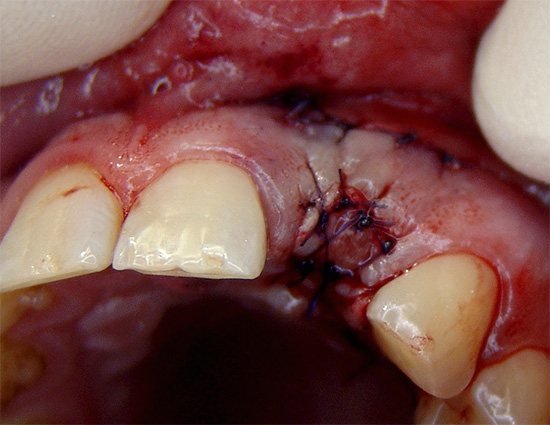

- De acordo com o depoimento, as costuras são sobrepostas no buraco, um guardanapo de gaze é instalado com ou sem a droga;

- Recomendações para o tratamento de feridas são fornecidas e são prescritos enxaguatórios e medicamentos anti-sépticos para aplicação tópica na forma de géis ou pomadas.